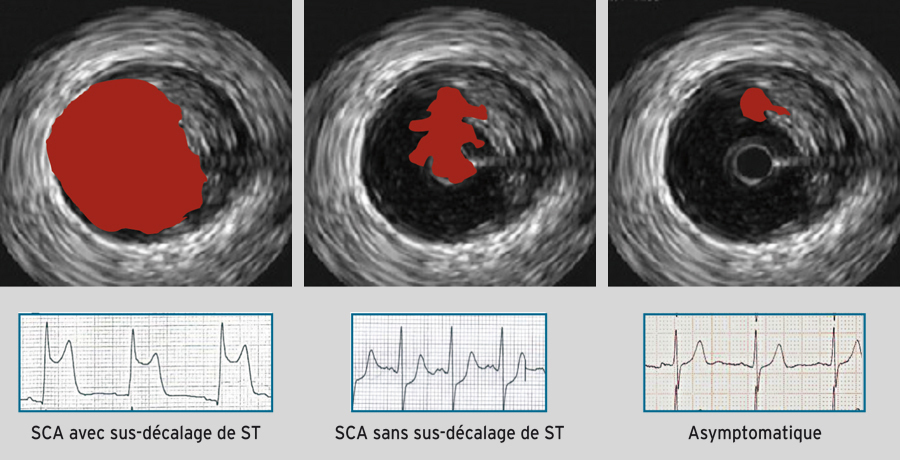

Aspect en échographie endocoronaire et relation entre l'électrocardiogramme et la clinique